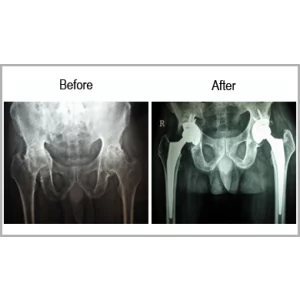

A Male Aged 52 Years Was Suffering From Ankylosing Spondylitis For More Than 30 Years. He Was Hardly Able To Walk Or Stand. His Both Hips Were Affected By Ankylosing Spondylitis.He Underwent Both Hip Replacements. Now He Is Totally Pain Free And Able To Walk For A Long Distance Without Any Kind Of Support.... Read more